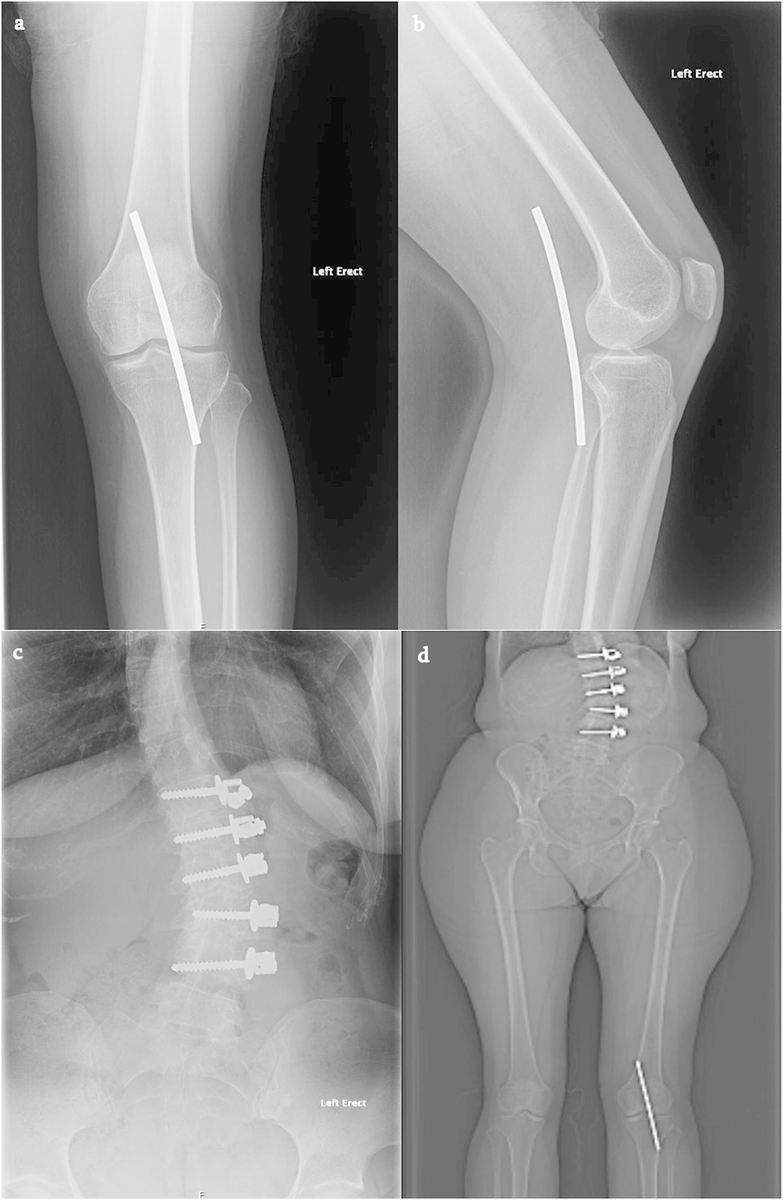

Can you answer our free question of the day? A patient presents to the trauma bay after involvement in a motor vehicle collision. Radiographs obtained in the trauma bay demonstrate a right distal femur fracture, as seen in Figure A. In surgery, the articular block is reduced, and reduction is held with headless compression screws. A retrograde intramedullary nail is then placed. After nail advancement, a varus and recurvatum deformity is noted at the fracture site with intraoperative fluoroscopy, as demonstrated via illustrations in Figures B and C. Placement of blocking screws in which locations (A - H) from Figure B and C would help correct this deformity? 1. B + E 2. A + G 3. B + F 4. C + H 5. D + H QID: 217509 Comment your answer below, then check to see if you got it correct by clicking the link below to see the answer & explanation. bit.ly/3OxP8sP #orthopedics #orthopedicsurgeon #orthopaedics #orthopaedic #orthopedic #ortholife #orthobullets #orthoresidents #orthoresident #orthoresidency #medicalschool #medicalstudent #medstudent #doctor